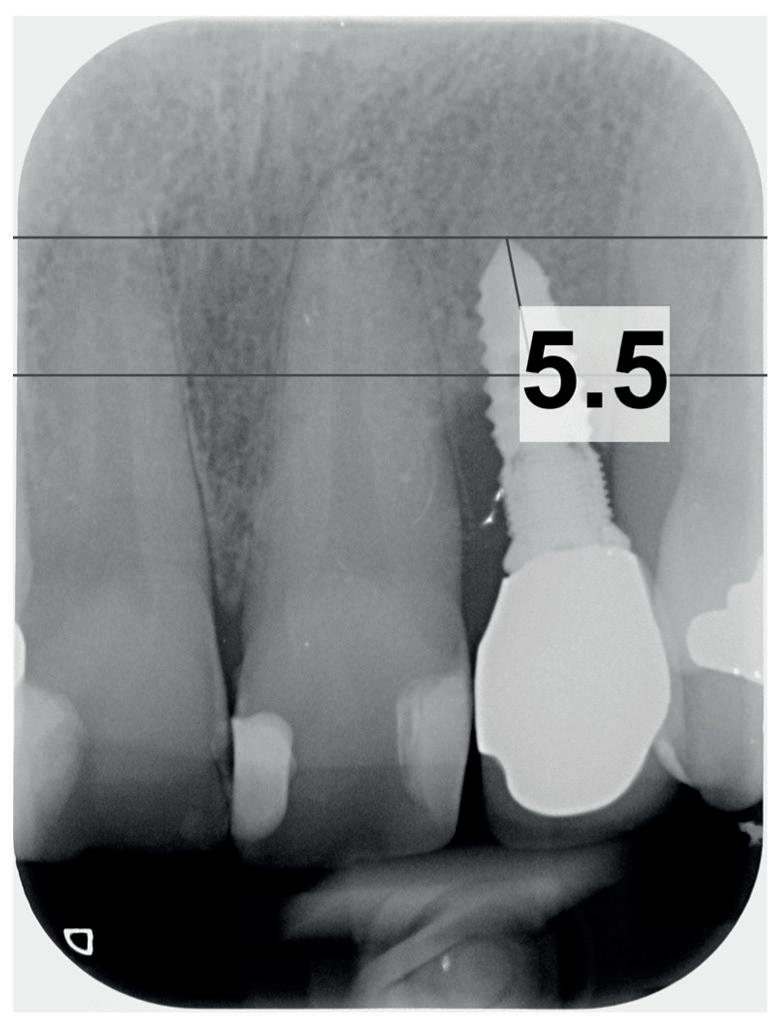

Bij klinisch en röntgenologisch onderzoek viel echter op dat radix van de 12 en 22 een convergerende (de radices staan dan naar mesiaal en naar elkaar toe) in plaats van divergerende (radices staan dan van elkaar af) stand had. Door deze convergerende stand van de radices was er in mesio-distale zin geen ruimte voor twee implantaten ter plaatse van de 11 en 21. Er werd daarom besloten, in tegenzin

1. Retainer met twee frontelementen

2. OPT radices 12 en 22 convergeren

3. Vaste apparatuur voor torque 12 en 22

4. OPT radices 12 en 22 divergeren na orthodontische behandeling

van de patiënt, om eerst weer vaste apparatuur terug te plaatsen om de radices in een divergerende stand te plaatsen. Gelukkig verliep deze behandeling voorspoedig. (afbeelding 2 -4). Het volgende behandelplan werd gemaakt: